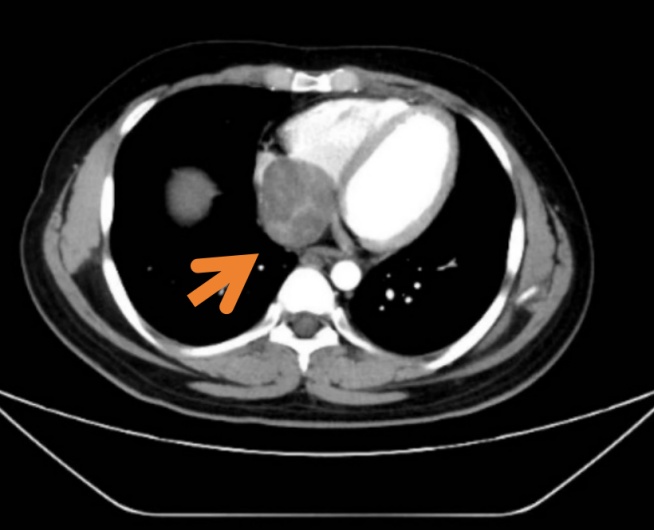

经过一遍遍仔细查找,医生在极其“逼仄”的范围,发现了“元凶”,也就是阿峰右肾上腺紧贴肝脏和右肾的位置,一个接近10公分的巨大肾上腺肿块,压迫在了周围血管、肝脏和肾脏。

右肾上腺皮质癌、下腔静脉癌栓、右心房癌栓

右心房癌栓

遗憾的是,年轻的阿峰属于极少数,在完善了穿刺活检后,他被确诊为“肾上腺皮质恶性肿瘤”(adrenocortical carcinoma, ACC),并且合并心脏、下腔静脉癌栓。这属于恶性肿瘤的一种,发病率极低,但恶性程度高、病情进展快、易局部转移。

最终,在一众医护人员的努力下,通过手术成功将这IV级癌栓成功切除。